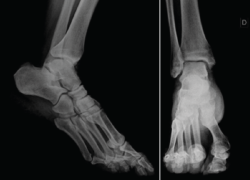

Se solicitó resonancia magnética (RM) y tomografía axial computarizada (TAC) del tobillo afecto a los 6 meses del traumatismo, en las que se observó una lesión osteocondral en la cúpula astragalina de 15 × 11 mm (diámetro anteroposterior y medial-lateral) según la RM y de 9 × 7 mm según la TAC (Figura 2). No se observó lesión capsuloligamentosa. Sí que se detectaron pequeños cuerpos libres en el receso capsular posteroexterno y anteromedial.

Figura 2. Imágenes de resonancia magnética (RM) en T2 (corte sagital y coronal). Imagen de la tomografía axial computarizada (TAC), corte coronal. Se observa una lesión osteocondral en la cúpula astragalina de 15 × 11 mm (diámetro anteroposterior y medial-lateral) según la RM y de 9 × 7 mm según la TAC.